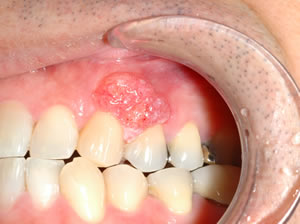

- 良性の腫瘍(エプーリス、線維腫など)

4. その他のできもの

「歯茎できもの 種類」と検索すると多くの情報が出てきますが、自己判断せずに専門家に見てもらうことが重要です。